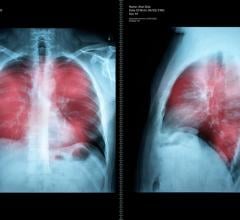

Lung Imaging

News and new technology innovations concerning how imaging technology for the lungs. This includes computed tomography (CT), X-ray and ultrasound imaging of the lungs to diagnose and monitor treatment for lung cancer, COPD, pulmonary embolism (PE), pneumonia, tuberculosis and COVID-19 can be found on this channel.